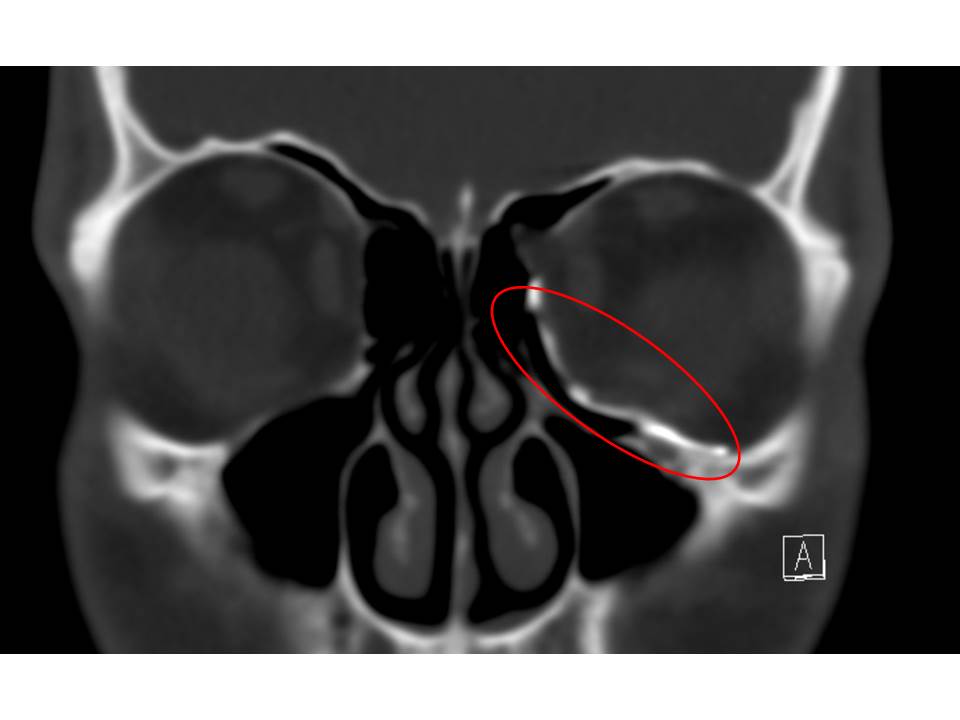

After a CT scan the healthy orbit is mirrored to the fractured one. The mirrored orbital floor is used as guide for a custom made craniofacial implant. The implant is designed on the computer and then 3D printed in titanium. The implant is inserted to the orbital floor and fixed with screws to the lower orbital rim (Figure 9).

The aim is to nearly normalise the orbital volume and remove adhesions to the fracture which can cause double vision by impacting the optic nerve. Clinical evaluation of eye movement and vision is used to assess the outcome and a CT scan is performed to assess the fit of the implant (Figure 10).

Figure 10: A postoperative CT scan illustrating the position of the custom-made craniofacial implant. The red circle marks the implant.